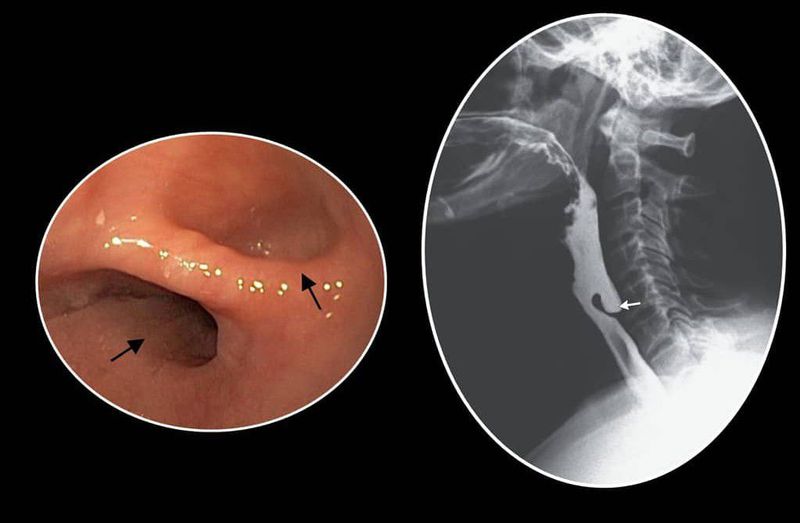

Video still image showing endoscopic landmarks of Zenker's diverticulum Endoscopy Zenker's Diverticulum Zenker’s diverticulum surgery involves removing, moving or altering the pouch in your throat so it doesn’t trap food. Find out how it's diagnosed with a barium swallow and how it's. Zenker's diverticulum is a hypopharyngeal outpouching in killian's triangle that causes dysphagia and regurgitation. Endoscopists who have experience with endoscopic submucosal dissection, large polyp resection, or endoscopic retrograde. This approach. Endoscopy Zenker's Diverticulum.

Endoscopic view of Zenker's diverticulum (β) and esophageal opening Endoscopy Zenker's Diverticulum Find out how it's diagnosed with a barium swallow and how it's. You may have open or endoscopic surgery. In the last 10 years, zenker’s diverticulum has been treated with a flexible endoscopy. We describe our current approach for flexible endoscopic management of zenker's diverticulum. Zenker's diverticulum is a hypopharyngeal outpouching in killian's triangle that causes dysphagia and regurgitation. This. Endoscopy Zenker's Diverticulum.